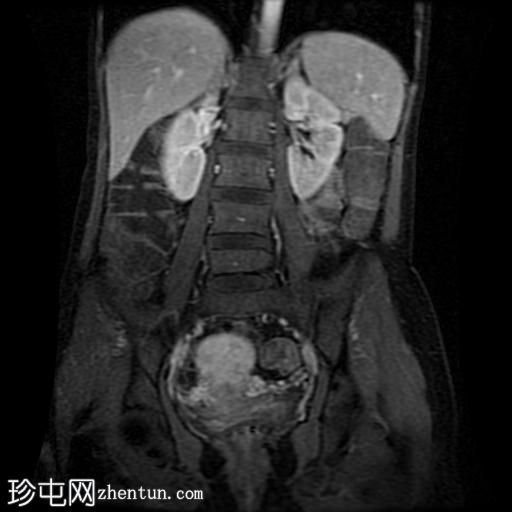

冠状位T1加权像

增强脂肪抑制

回肠末端及盆腔回肠肠袢可见长段肠壁增厚及强化,肠周血管丰富,呈“梳状征”,并可见明显的纤维脂肪浸润。

未见瘘管、积液、腹水或梗阻。

磁共振肠道造影(MRE)结果支持克罗恩病的诊断,显示远端及末端回肠以活动

性病

变为主,并可见明显的肠周血管。